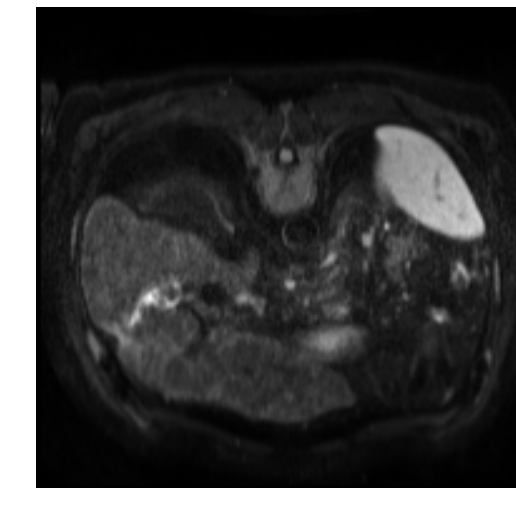

In clinical routine, manual or semi-manual segmentation techniques are applied to interprete CT and MRI images that have been acquired in the diagnosis of the liver. These techniques, however, are subjective, operator-dependent and very time-consuming. In order to improve the productivity of radiologists, computer-aided methods have been developed in the past. However, an automated robust segmentation of combined liver and lesion remains still an open problem because of challenges as a low-contrast between liver and lesion, different types of contrast levels (hyper-/hypo-intense tumors), abnormalities in tissues (such as after surgical resection of metastasis), size and varying number of lesions. As shown in figure 1 the heterogeneity in liver and lesion contrast is very large among subjects. Different acquisition protocols, differing contrast-agents, varying levels of contrast enhancements and dissimilar scanner resolutions lead to unpredictable intensity differences between liver and lesion tissue. This complexity of contrast differences make it difficult for intensity-based methods to generalize to unseen test cases from different clinical sites. In addition, the varying shape of lesions due to irregular tumor growth and response to treatment (i.e surgical resection) reduce efficiency of computational methods that make use of prior knowledge on lesion shape.

Refer to caption

Figure 1: Liver and liver lesions slices in CT and diffusion weighted DW-MRI as well as the corresponding histogram for liver and lesions pixels in the respective modality. The shape, size and level of contrast vary for different lesions. As the histograms indicate, there is a significant overlap between liver and lesion intensities, leading to a low overall contrast.